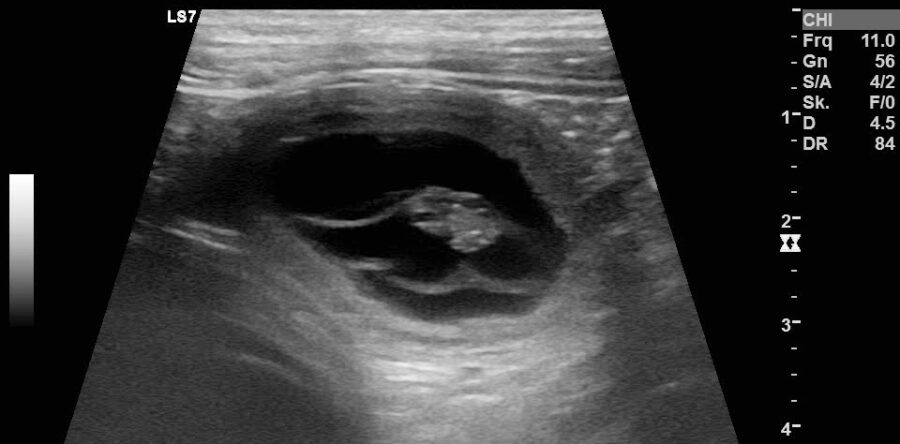

Branka erwartet am Dienstag den 22.02.2022 ihren ersten Nachwuchs. Der Deckrüde ist Isko vom Ellenbach von Lisa Adam aus Goldenstedt.